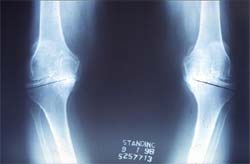

70岁,软骨破坏,严重双膝内翻畸形

双膝关节X线片显示关节软骨破坏,间隙消失,膝内翻

骨性关节炎关节软骨破坏,股骨头坏死 股骨颈骨折,容易发生不愈合